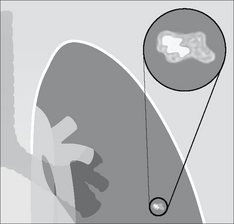

image

Figure 20.1 A SPN is a common finding on adult CXRs. Approximately 60–70% are benign. Some 30–40% are malignant2-4.